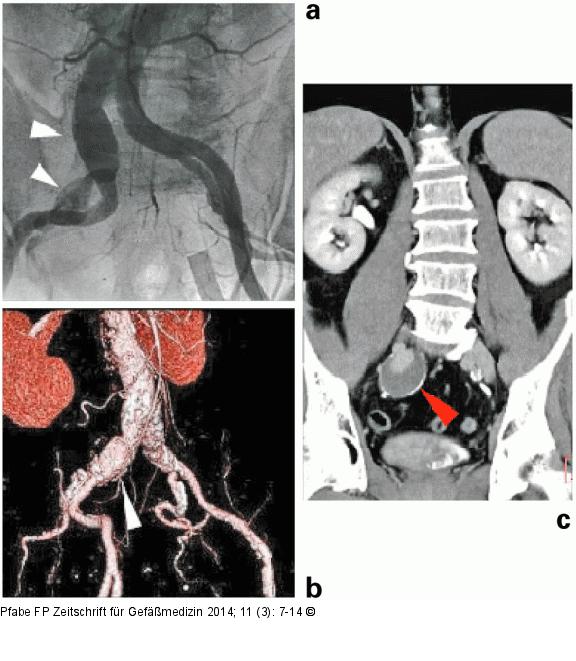

Abbildung 5: Iliakalaneurysma (a) Angiographischer Befund (Luminographie) eines Aneurysmas der A. iliaca communis und interna rechts (weißer Pfeil), (b) multiplane Rekonstruktion (3D-VRT) eines Aneurysmas der A. iliaca communis rechts (weißer Pfeil); (c) Nachweis von Wandpathologien des Aneurysmasacks mittels CT-Angiographie (roter Pfeil = Kalzifikation und wandständiger Thrombus). |

Abbildung 5: Iliakalaneurysma

(a) Angiographischer Befund (Luminographie) eines Aneurysmas der A. iliaca communis und interna rechts (weißer Pfeil), (b) multiplane Rekonstruktion (3D-VRT) eines Aneurysmas der A. iliaca communis rechts (weißer Pfeil); (c) Nachweis von Wandpathologien des Aneurysmasacks mittels CT-Angiographie (roter Pfeil = Kalzifikation und wandständiger Thrombus). |